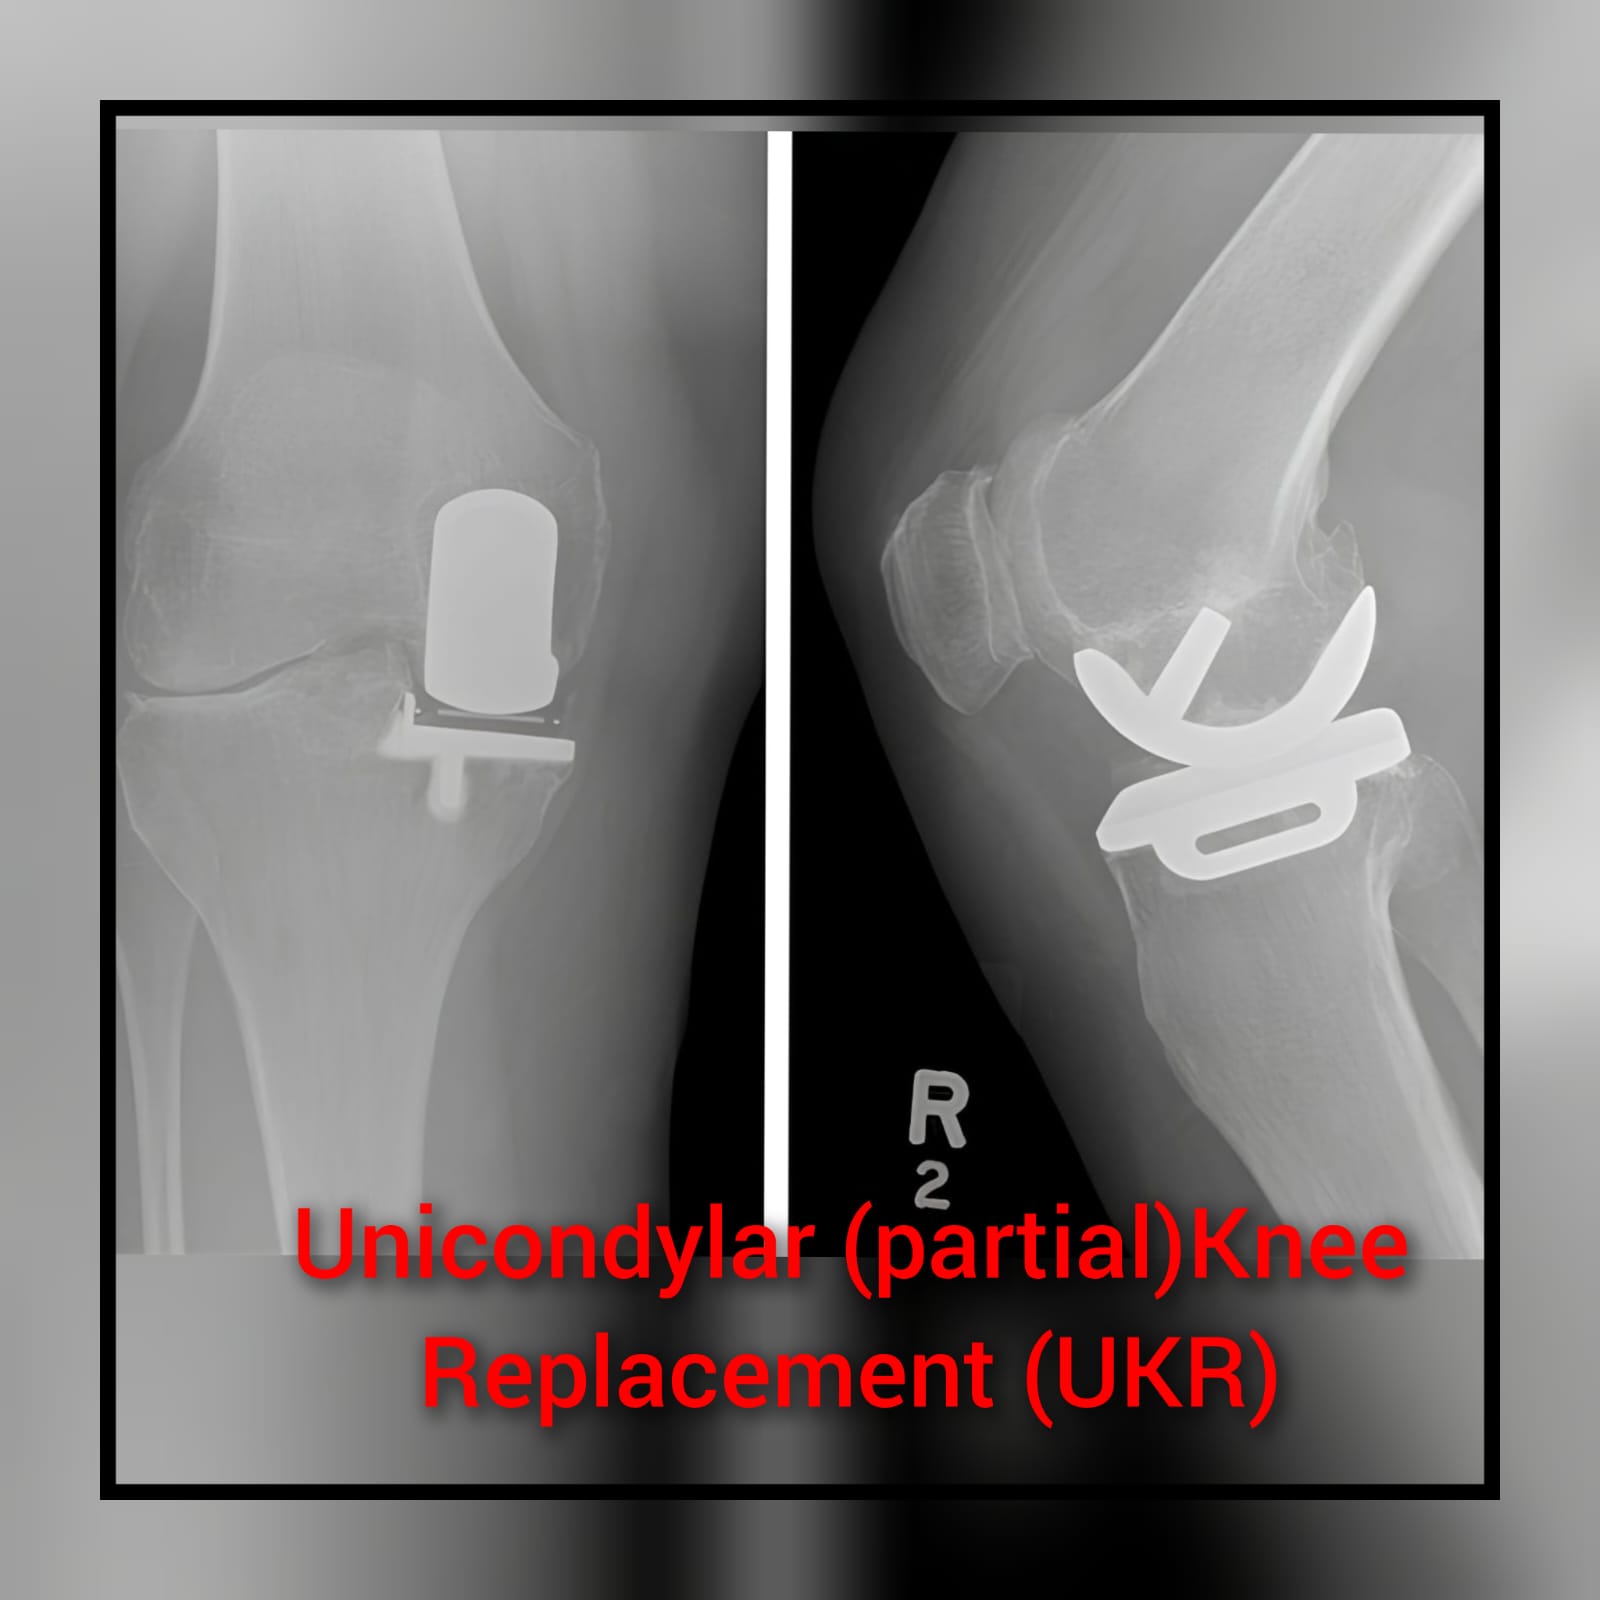

Total Knee Replacement